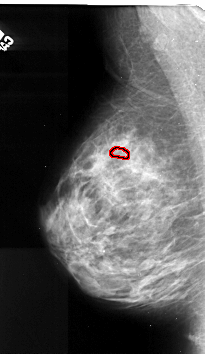

A_1105_1.LEFT_CC

LEFT_CC LINES 4741 PIXELS_PER_LINE 2821 BITS_PER_PIXEL 16 RESOLUTION 42 OVERLAY

FILE: A_1105_1.LEFT_CC.OVERLAY

TOTAL_ABNORMALITIES 1

ABNORMALITY 1

LESION_TYPE CALCIFICATION TYPE PLEOMORPHIC DISTRIBUTION CLUSTERED

ASSESSMENT 4

SUBTLETY 2

PATHOLOGY MALIGNANT

TOTAL_OUTLINES 1

BOUNDARY